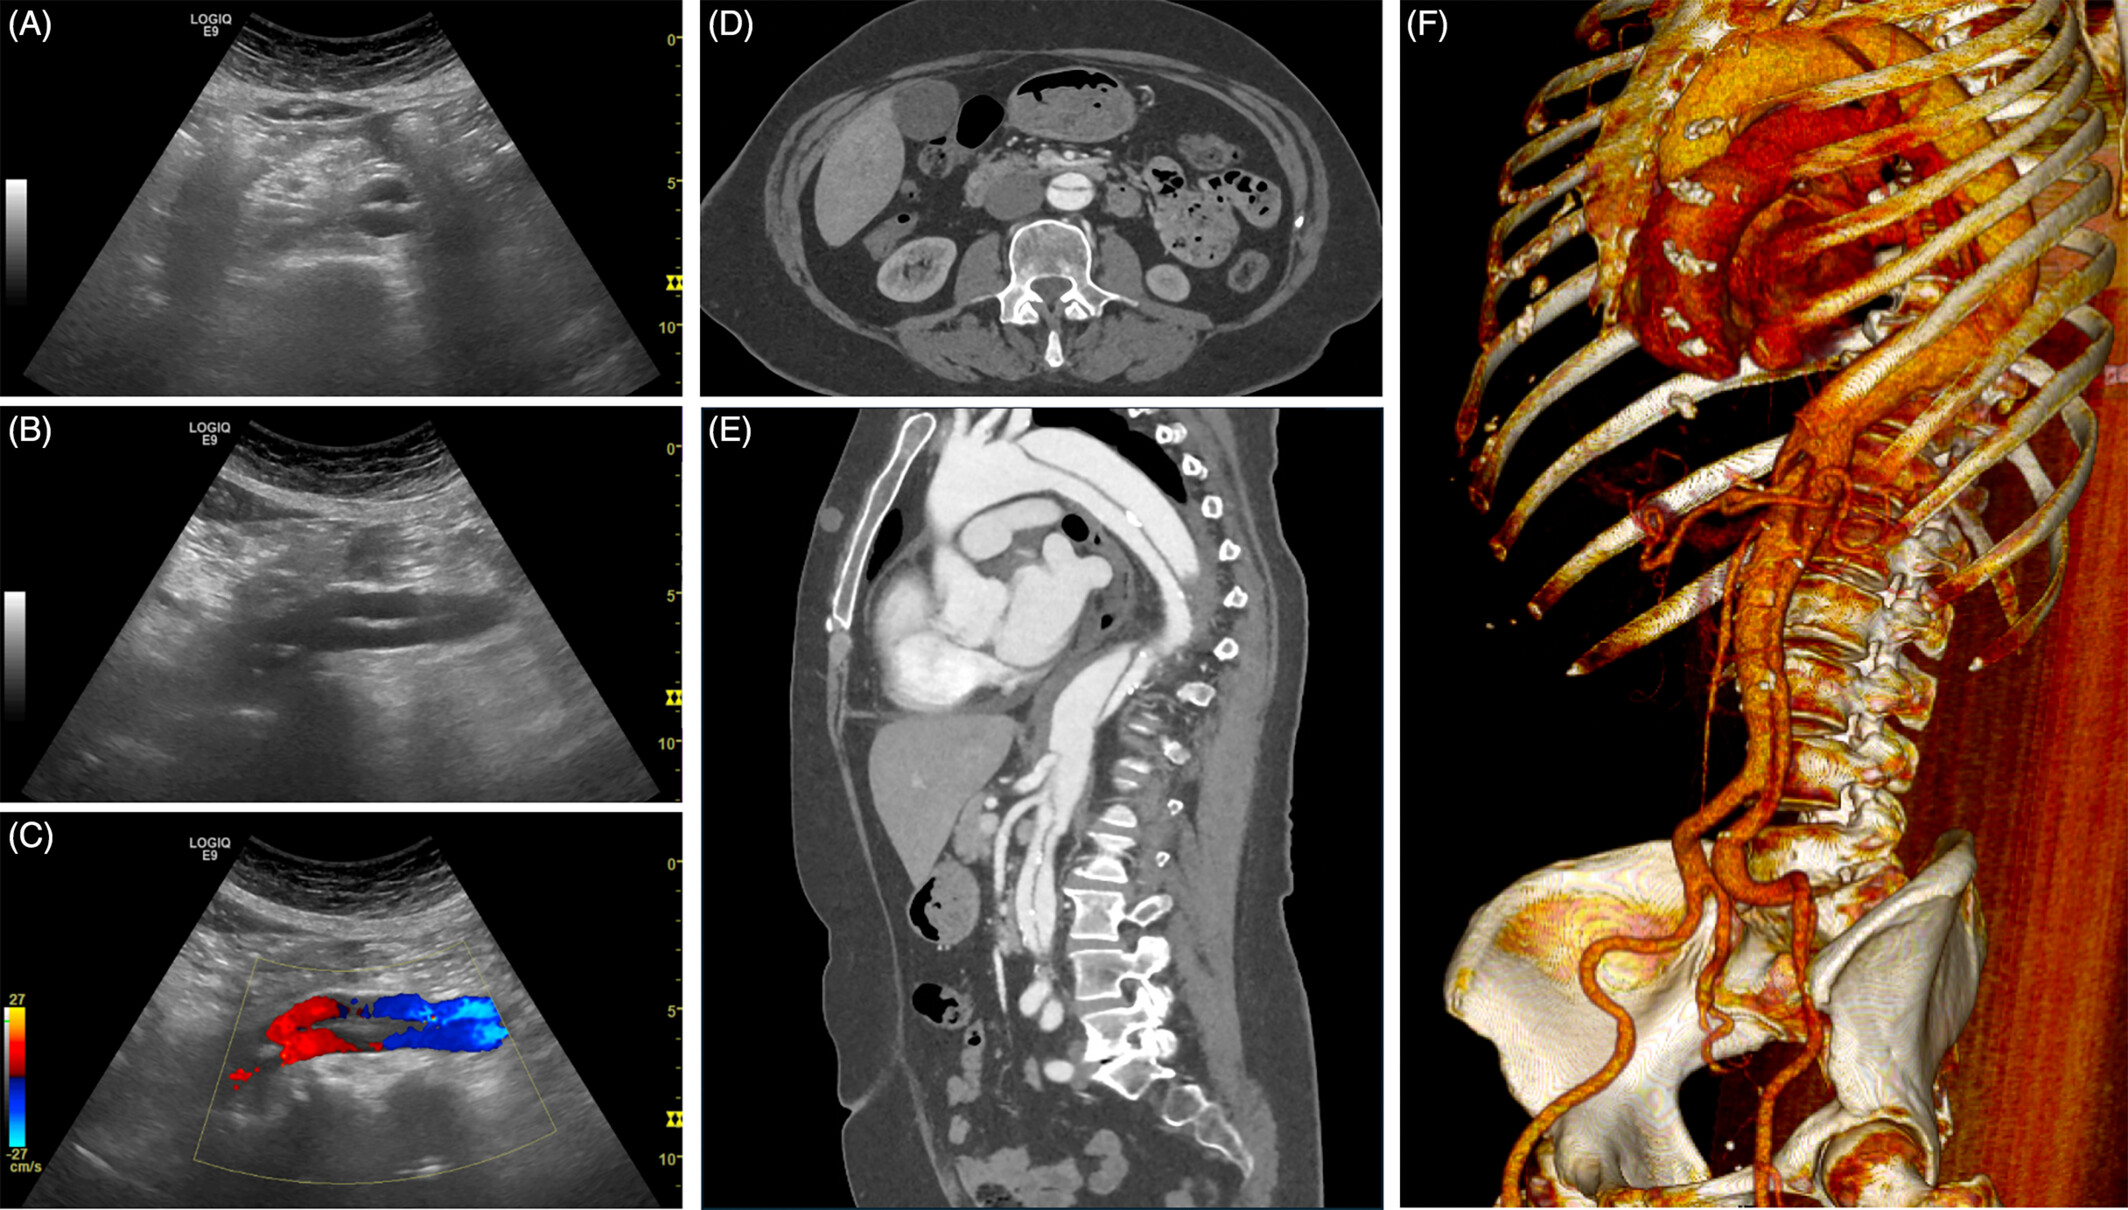

복부 대동맥 초음파 검사는 방사선 노출 없이 짧은 시간에 혈관 직경·벽 구조·혈류를 확인할 수 있어 응급상황을 예방하는 1차 선별검사로 각광받고 있습니다.

복부 대동맥류(AAA)

대동맥 박리(Aortic dissection)

- 내막이 찢겨 혈관벽이 이중 통로(true·false lumen)로 분리되는 응급 질환입니다.

- 흉통·등통증이 번개처럼 발생하며, 초음파는 내막 판막(intimal flap)과 혈류 차이를 즉시 확인해 조기 진단이 가능합니다.

- 초음파 도플러(Modified Bernoulli)로 혈류 속도를 계산해 협착률을 추정합니다.